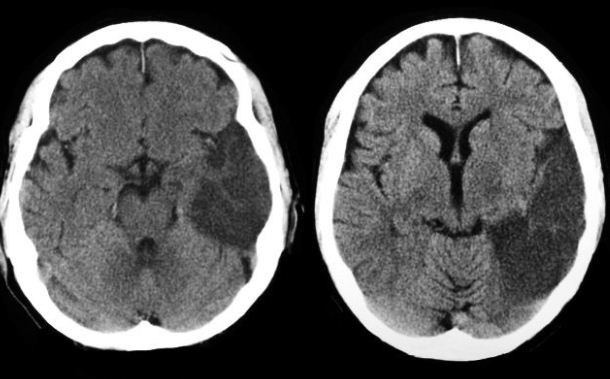

Computed axial tomography (CAT)

• Computed tomography CT

• X-ray based

CT scan of stroke